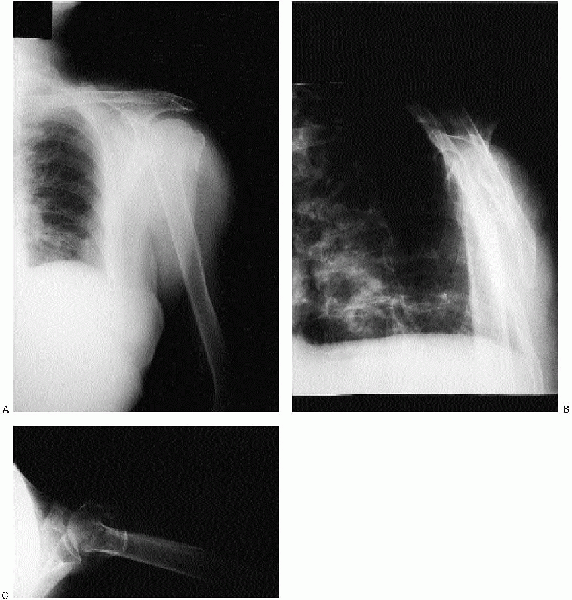

(AP) and lateral views of the shoulder obtained in the plane of the

scapula and an axillary view (Fig. 5-4). The

scapular AP view offers a general overview of the fracture and is

usually evaluated first. The scapular lateral assists in delineating

the position of the humeral head relative to the glenoid and is

particularly useful in showing dislocations or posteriorly displaced

fragments. The axillary view also permits assessment of the

glenohumeral relationship. Computed tomography (CT) scans of proximal

humeral fractures and fracture dislocations may be indicated when the

trauma series radiographs are indeterminate. CT scans have also been

recommended to evaluate the rotation of fragments and the degree of

tuberosity displacement, as well as articular impression fractures,

head-splitting fractures, and chronic fracture-dislocations.

![]() |

|

FIGURE 5-4. Anteroposterior (A), Y view (B), and axillary (C) revealing a displaced three-part fracture of the proximal humerus.